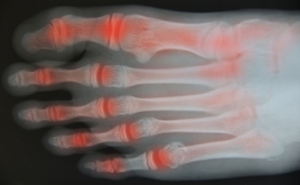

Toe arthritis is a condition where the joints in the toes become inflamed, causing pain and stiffness. The most common cause is osteoarthritis, which occurs as the cartilage in the toe joints wears down over time, often due to age or repetitive stress. Other causes include rheumatoid arthritis or injury to the toe. Symptoms of toe arthritis include pain in the affected joint, particularly during movement, swelling, and a reduced range of motion. In some cases, the joint may become deformed or misaligned. Relief from toe arthritis involves wearing proper footwear that provides support and cushioning, as well as anti-inflammatory medications to reduce pain and swelling. Specific exercises can also help improve joint flexibility and strength. In severe cases, surgical options may be considered to restore function and alleviate pain. If you have symptoms of arthritis in your toes, it is suggested that you consult a podiatrist who can offer you effective relief and management tips.

Arthritic Foot Care

Arthritis is a joint disorder that involves the inflammation of different joints in your body, such as those in your feet. Arthritis is often caused by a degenerative joint disease and causes mild to severe pain in all affected areas. In addition to this, swelling and stiffness in the affected joints can also be a common symptom of arthritis.